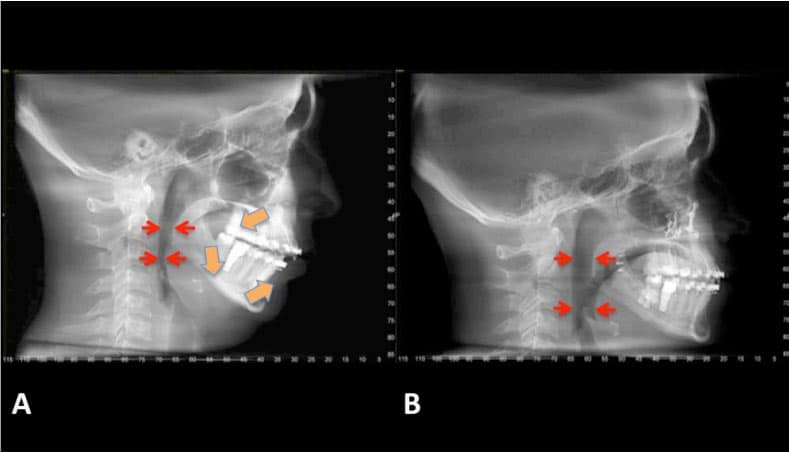

"Obvious" class 2 or class 3 often end up with ideal airways after surgery, which improves breathing significantly.

Gives you an airway that the average person can only dream of.